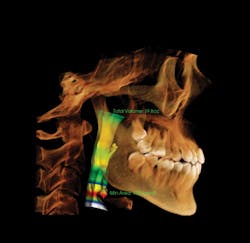

13x15 covers the entire maxillofacial region.

Larger fields of view offer broader diagnostic capabilities, including airways.

When my assistant takes a scan, I can look-immediately, and before the patient is even reseated in his or her room, I can say, "Yes, we can do this," or, "No, we can't." To have greater efficiency and clarity courtesy of one technology is incredible.

The overwhelmingly positive reception by our patient base and the ways we see the practice continuing to evolve are reminders why 3-D imaging is such a powerful tool in our treatment plans. With the scans, photography, and support from our lab in producing wax-ups, our patients can truly begin treatment with the end in mind. There is a good percentage of people who won't pay exorbitant fees for dental work, but they will pay for quality treatment and competent care when you and your team create value.